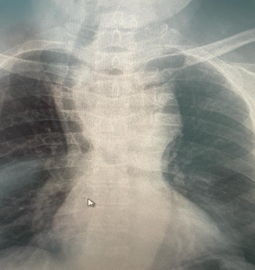

Chest X-ray: No pleural effusion or pneumothorax. Both lungs are clear, with no focal lesion. Widening of the superior mediastinum with deviation of the trachea to the left (Figure 1).

Figure 1 Chest XR.